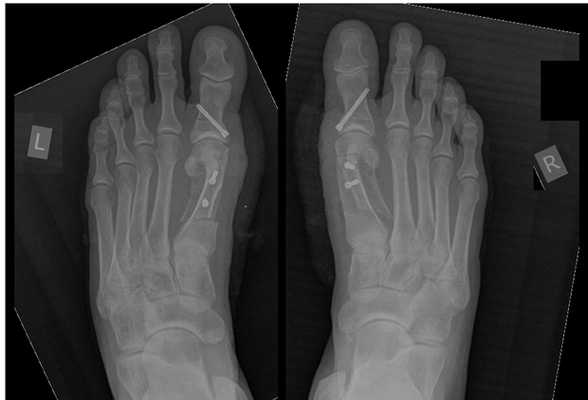

На второй стадии Халюс Вальгус происходит дальнейшее отклонение 1 плюсневой кости кнутри (межплюсневый угол 13-15 градусов) и кверху с дальнейшим увеличением угла вальгуса (26-40 градусов). На этой стадии также возможно вовлечение 2-3-4-5 лучей стопы. За счёт постепенного распластывания поперечного свода 5 плюсневая кость начинает отклоняться кнаружи, а 5 палец при этом смещается кнутри, картина зеркальная деформации 1 луча. 2-3-4 плюсневые кости при этом постепенно начинают опускаться вниз. Это приводит к их перегрузке, которая может провляться болями и формированием "натоптыша" под головками 2-3 плюсневых костей.